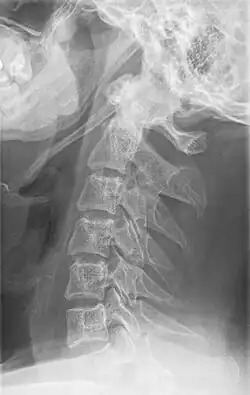

Radiograph, lateral view showing joint-like formation in ossified stylohyoid ligament

Imaging is important and is diagnostic. Visualizing the styloid process on a CT scan with 3D reconstruction is the suggested imaging technique.[13] The enlarged styloid may be visible on an orthopantogram or a lateral soft tissue X ray of the neck.